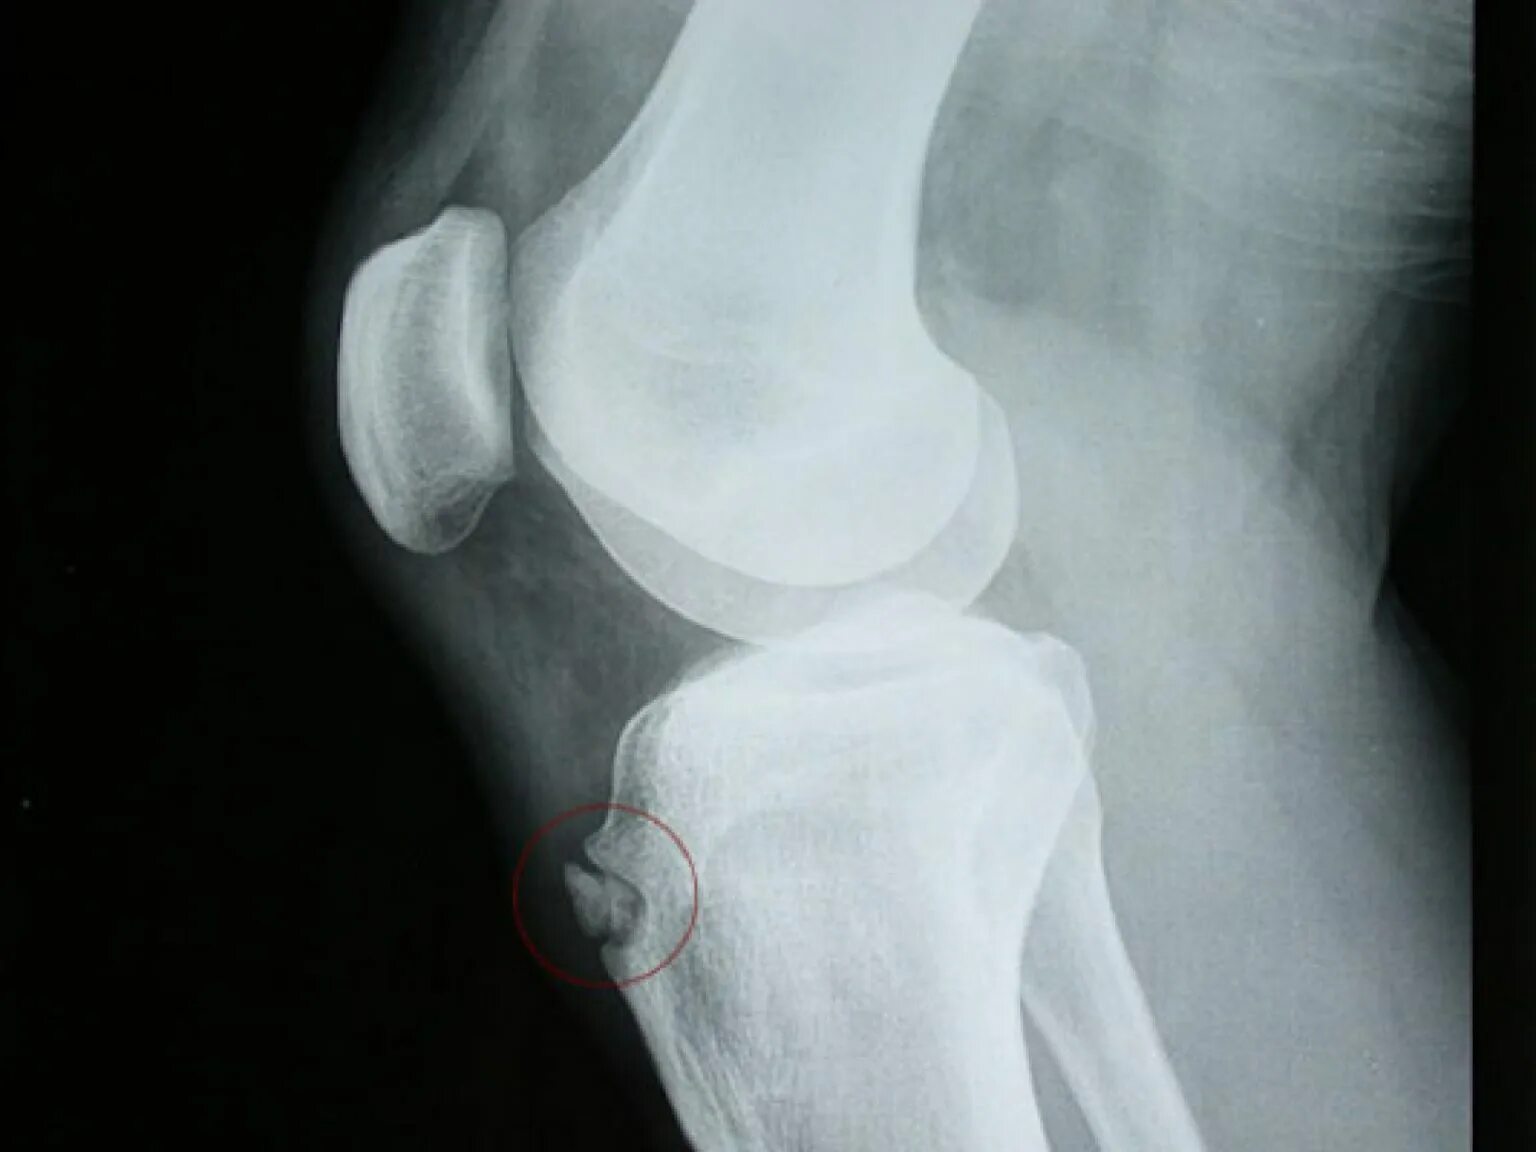

Болезнь осгут шляттера